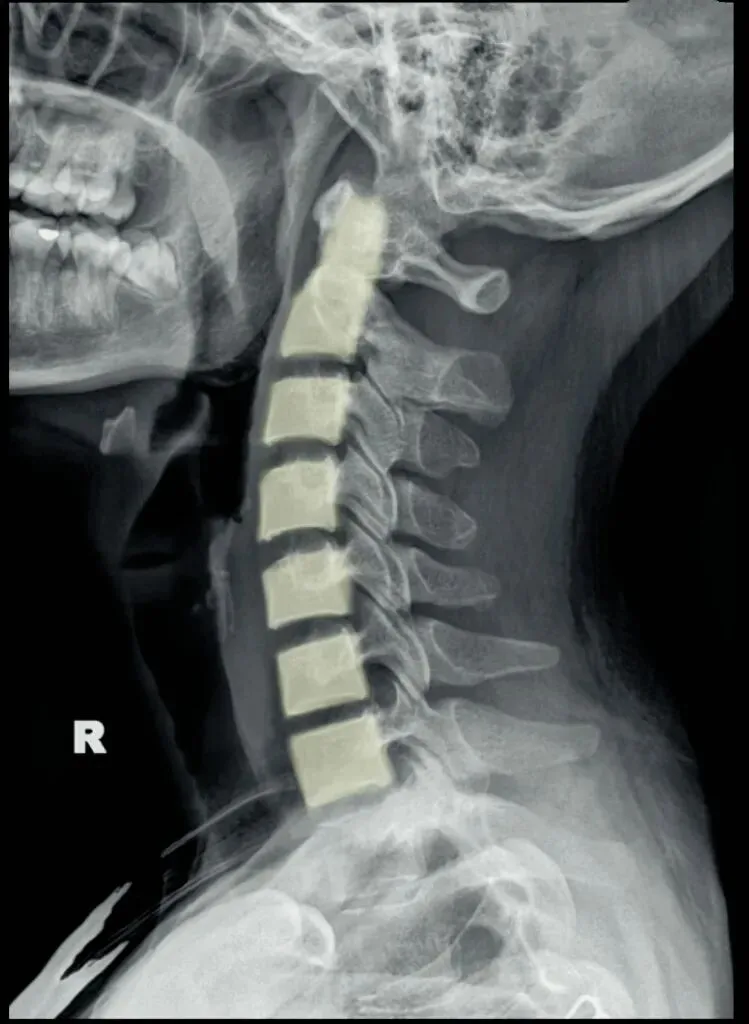

五间是指颈椎椎间隙的变化,主要在颈椎侧位片上观察椎间隙变化同时也反映了椎间盘的变化。

颈椎的退变最早发生在C56椎间盘上,因此C56椎间隙也最早发现变窄的征象。

颈椎骨性椎体为前低后高,

而椎间盘则为前高后低,因此颈椎的生理性前凸是由椎间盘的前高后低所形成的。

在正常情况下,C23、C34和C45间隙大致相等,椎间隙前部为3.8毫米正负0.5毫米,

后缘间隙为1.9毫米正负0.28毫米。

C56间隙较上为宽,而C67间隙最宽,但C7与T1间隙又较窄。